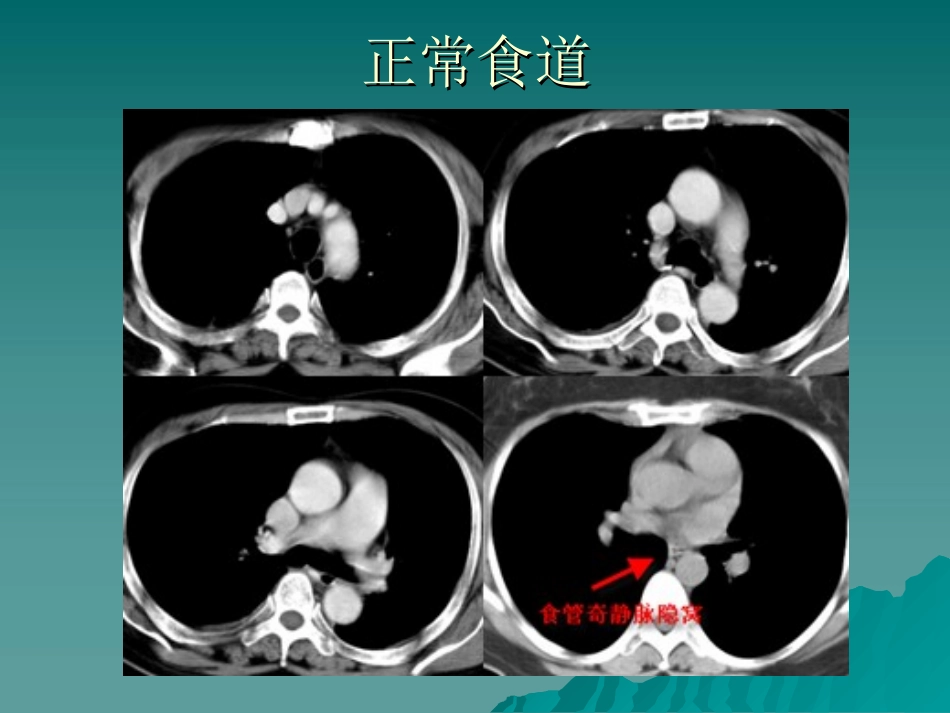

正常食道正常食道位于后纵隔,气管后椎体前位于后纵隔,气管后椎体前分颈、胸和腹段三部分,胸段分别以第分颈、胸和腹段三部分,胸段分别以第66、、88椎体水平分上、中和下三段;三个压迹椎体水平分上、中和下三段;三个压迹食管壁因扩张程度不同而厚薄不一,但通食管壁因扩张程度不同而厚薄不一,但通常少于常少于3mm3mm,如壁厚超过,如壁厚超过5mm5mm则认为则认为异常异常正常食道正常食道食管静脉曲张食管静脉曲张CTCT表现表现门静脉高压的主要并发症,肝门静脉高压的主要并发症,肝硬化硬化呕血、黑便,失血性休克或死呕血、黑便,失血性休克或死亡亡下段食道周围迂曲增粗静脉血下段食道周围迂曲增粗静脉血管,肝硬化表现管,肝硬化表现食管胃底静脉曲张食管胃底静脉曲张食道静脉曲张食道静脉曲张食道静脉曲张食道静脉曲张食道癌食道癌CTCT表现表现食道壁的增厚,管腔变形、移位食道壁的增厚,管腔变形、移位梗阻以上管腔扩张梗阻以上管腔扩张向周围浸润的表现向周围浸润的表现淋巴结转移(淋巴结长径≥淋巴结转移(淋巴结长径≥15mm15mm))食道癌食道癌食道上段癌食道上段癌食道中段癌食道中段癌正常胃正常胃胃服对比剂后适度扩张,胃壁显示良好,厚度均匀,正常厚度范围胃2-5mm。超过10mm为异常。胃癌胃癌胃癌是消化系统最常见的恶性肿瘤。胃癌是消化系统最常见的恶性肿瘤。男:女=男:女=22::11。一般发病年龄在。一般发病年龄在40~6040~60岁,青壮年发病并不少见。岁,青壮年发病并不少见。早期症状并不明显特异,上腹部隐痛不适、早期症状并不明显特异,上腹部隐痛不适、食欲不振、恶心呕吐,常吐出棕褐色食物食欲不振、恶心呕吐,常吐出棕褐色食物残渣。晚期出现贫血、上腹肿块、恶病质、残渣。晚期出现贫血、上腹肿块、恶病质、粪便潜血持续阳性等。粪便潜血持续阳性等。胃癌可发生于胃的任何部位,以胃小弯胃胃癌可发生于胃的任何部位,以胃小弯胃窦部最常见,贲门胃底区占第二位。窦部最常见,贲门胃底区占第二位。胃癌胃癌CTCT表现表现胃壁增厚:胃壁增厚:局限或弥漫,粘膜面凹凸不平局限或弥漫,粘膜面凹凸不平腔内肿块:腔内肿块:表面不光滑,分叶、结节或菜表面不光滑,分叶、结节或菜花状,表面可有溃疡花状,表面可有溃疡胃腔狭窄:胃腔狭窄:胃壁增厚基础上的胃腔狭窄,胃壁增厚基础上的胃腔狭窄,非对称性狭窄,胃壁僵硬且不规则非对称性狭窄,胃壁僵硬且不规则胃壁异常强化:胃壁异常强化:粘膜面病灶在注射造影剂粘膜面病灶在注射造影剂35-45s35-45s即可明显强化,而侵及肌层的病变,即可明显强化,而侵及肌层的病变,强化高峰时间在强化高峰时间在50-60s50-60s之后出现,较正之后出现,较正常胃壁强化明显且时间延长。常胃壁强化明显且时间延长。胃癌胃癌胃癌肝转移、淋巴转移胃癌肝转移、淋巴转移残胃癌、淋巴结转移残胃癌、淋巴结转移胃癌肝转移胃癌肝转移肠癌肠癌小肠腺癌小肠腺癌起源于肠黏膜上皮细胞起源于肠黏膜上皮细胞好发十二指肠及空肠好发十二指肠及空肠腔内突出结节或肠壁浸润增厚腔内突出结节或肠壁浸润增厚便血、肠梗阻、黄疸及腹部肿块便血、肠梗阻、黄疸及腹部肿块结肠癌结肠癌好发乙状结肠及直肠好发乙状结肠及直肠增生型增生型浸润型浸润型溃疡型溃疡型便血、腹泻、便秘便血、腹泻、便秘直肠癌直肠癌--粪便变细、里急后重粪便变细、里急后重升结肠癌升结肠癌降结肠癌降结肠癌降结肠癌并淋巴转移降结肠癌并淋巴转移直肠癌直肠癌直肠癌、淋巴结转移直肠癌、淋巴结转移直肠癌术后复发直肠癌术后复发胃肠道间质瘤胃肠道间质瘤胃肠道间叶组织来源胃肠道间叶组织来源好发中老年人,多见于胃及小肠好发中老年人,多见于胃及小肠部分为恶性,可见血行或淋巴转移部分为恶性,可见血行或淋巴转移胃、肠壁软组织肿块,腔内、外生长胃、肠壁软组织肿块,腔内、外生长边界清晰、密度大部分均匀、中重度强化,边界清晰、密度大部分均匀、中重度强化,可见囊变、坏死,与肠管沟通可见气液平可见囊变、坏死,与肠管沟通可见气液平面面胃间质瘤胃间质瘤胃间质瘤胃间质瘤肠...